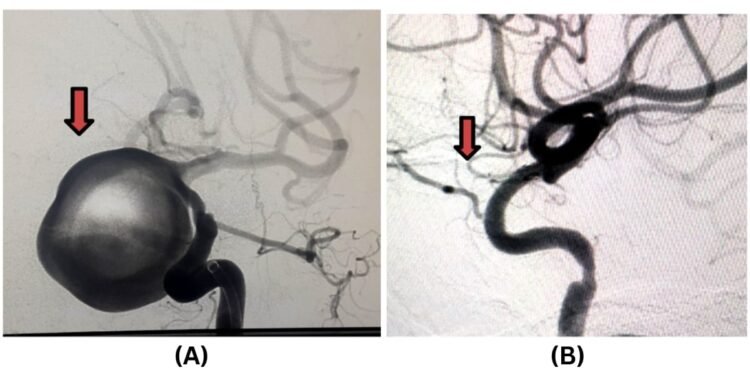

- Aneurysm Management: Coiling fills aneurysms; flow diverters redirect blood flow.

Central to this capability is Jehangir Hospital’s dedicated Neuro Cath Lab, equipped with a Digital Subtraction Angiography (DSA) system. This allows for:

- High-definition, 3D angiography of cerebral and spinal vessels.